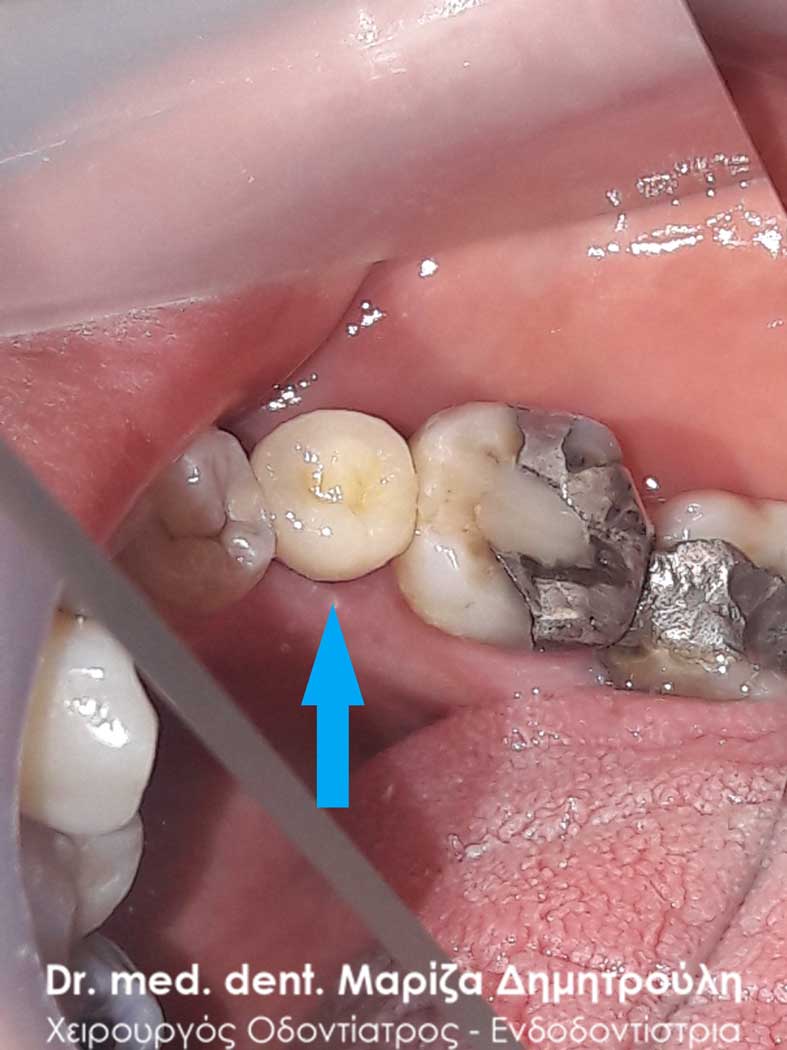

Περιστατικό – Ολοκεραμική θήκη ζιρκονίου στον αριστερο γομφίο της κάτω γνάθου

Ο πρώτος γόμφιος στην αριστερή πλευρά της κάτω γνάθου είχε απονευρωθεί στο παρελθόν. Ο ασθενής δεν θέλησε να καλύψει το δόντι με θήκη, ώστε να είναι πλήρως προστατευμένο με αποτέλεσμα το δόντι να σπάσει (όπως φαίνεται στην αρχική εικόνα). Η λύση θεραπείας ήταν η κατασκευή στεφάνης δοντιού, αφού προηγουμένως το δόντι τροχίστηκε καταλλήλως και ο οδοντοτεχνίτης κατασκεύασε την ολοκεραμική θήκη ζιρκονίου.

Το δόντι είναι πλέον πλήρως προστατευμένο και μπορεί να αντέξει στο πέρασμα των χρόνων.

ΜΕΤΑ